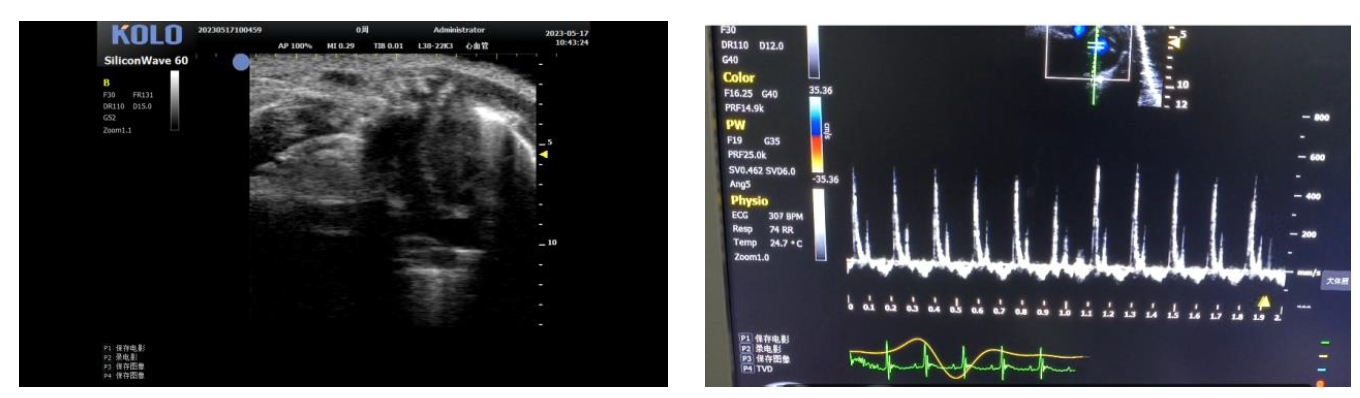

2. 小鼠心脏研究---四腔心(长轴+血流测速)